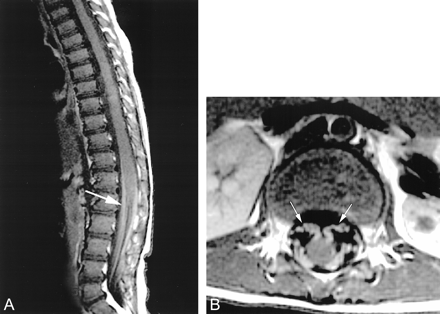

T1-weighted MR images (450/20) of the lumbosacral region reveal striking contrast enhancement of the lumbosacral nerve roots (arrows).

A, Sagittal view.

B, Axial view.